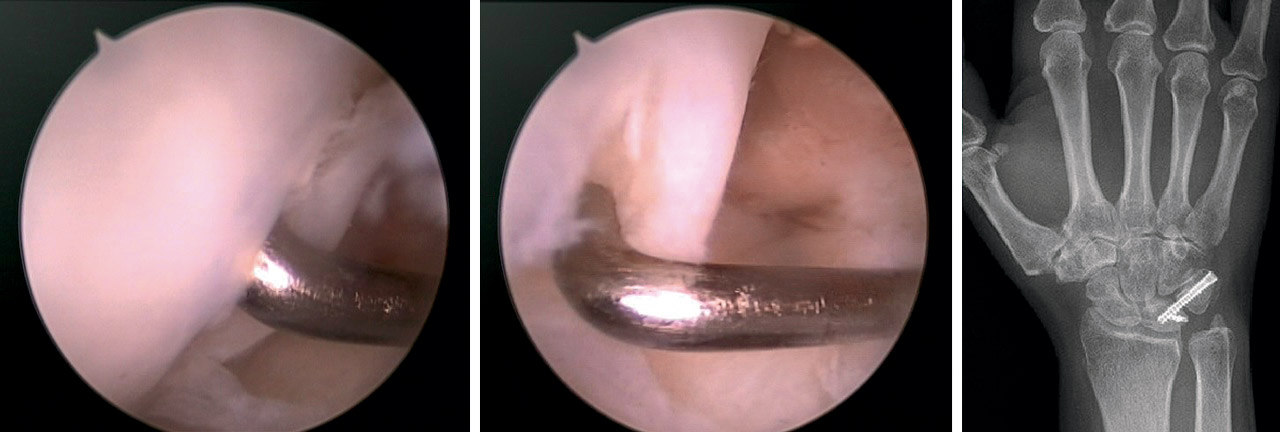

Fragmentos osteocondrales libres

Se realizó reducción y fijación en los casos viables, o resección artroscópica en caso contrario. La viabilidad del fragmento se estableció en función de la dimensión, la integridad, la fragmentación del cartílago articular y la posibilidad de fijación.

En casos de fragmentos osteocondrales con suficiente entidad, se intentó la reducción artroscópica directa y la fijación con tornillo ocultable percutáneo o con varillas de material reabsorbible(32). De lo contrario, fueron extraídos.